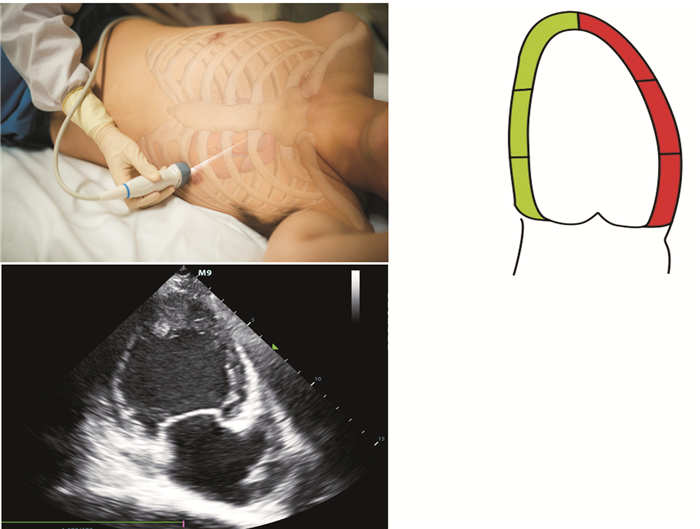

2.2.2 heart (心脏)

采用胸骨旁长轴、短轴、心尖四腔心等切面,通过对心脏的大小、形态、室壁运动、主动脉内径增宽、有无内膜撕脱、心脏收缩及舒张节律及频率、三尖瓣反流情况等项目进行评估,协助明确休克病因及类型,具体急诊床旁心脏超声评估见SMART原则,筛查有无心肌梗死及恶性心律失常等心源性休克的直接证据及梗阻性休克、分布性休克的间接证据 (表 4图 6~8)。

图 6 心脏胸骨旁长轴切面

图 7-1 心脏胸骨旁短轴主动脉瓣水平切面

图 7-2 心脏胸骨旁短轴二尖瓣水平切面

图 7-3 心脏胸骨旁短轴乳头肌水平切面

图 7-4 心脏胸骨旁短轴心尖水平切面

图 8 心脏心尖四腔心切面